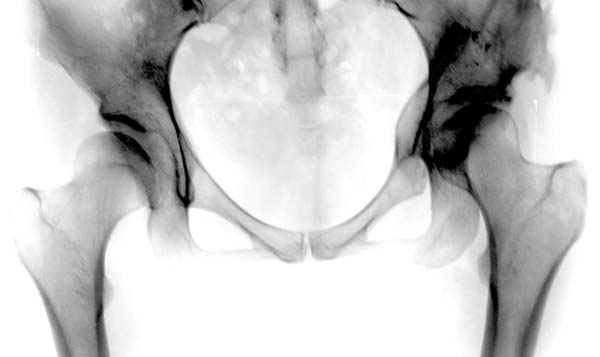

предоперационные снимки #8

предоперационные снимки #9

предоперационные снимки #10

№ 8-10 предоперационные снимки